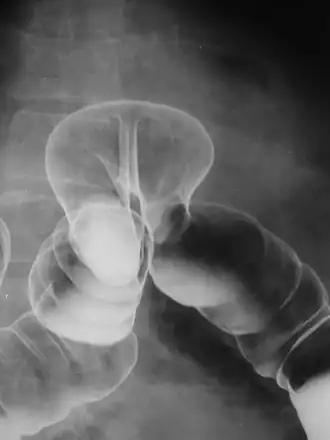

Radiograph of a barium enema displaying a colonic herniation. | |

A lower gastrointestinal series is a medical procedure used to examine and diagnose problems with the human colon of the large intestine. Radiographs (X-ray pictures) are taken while barium sulfate, a radiocontrast agent, fills the colon via an enema through the rectum.

Barium enemas are most commonly used to check bowel health; they can help diagnose and evaluate the extent of inflammatory bowel diseases such as ulcerative colitis and Crohn's disease. Polyps can be seen, though not removed during the exam like with a colonoscopy—they may be cancerous. Other problems such as diverticulosis (small pouches formed on the colon wall that can become inflamed) and intussusception can be found (and in certain cases the test itself can treat intussusception). An acute appendicitis or twisted loop of the bowel may also be seen. If the picture is normal a functional cause such as irritable bowel syndrome (IBS) may be considered.

In a healthy colon, barium should fill the colon uniformly and show normal bowel contour, patency (should be freely open), and position.